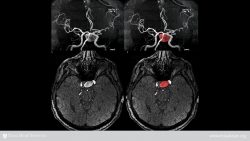

An aneurysm is a balloon-like bulge in an artery. Aneurysms can form in arteries of all sizes. An aneurysm occurs when the pressure of blood passing through part of a weakened artery forces the vessel to bulge outward, forming what you might think of as a blister. Not all aneurysms are life threatening. But if the bulging stretches the artery too far, this vessel may burst, causing a person to bleed to death. An aneurysm that bleeds into the brain can lead to stroke or death.

- In the tiny arteries that supply blood to the brain (the cerebral arteries).